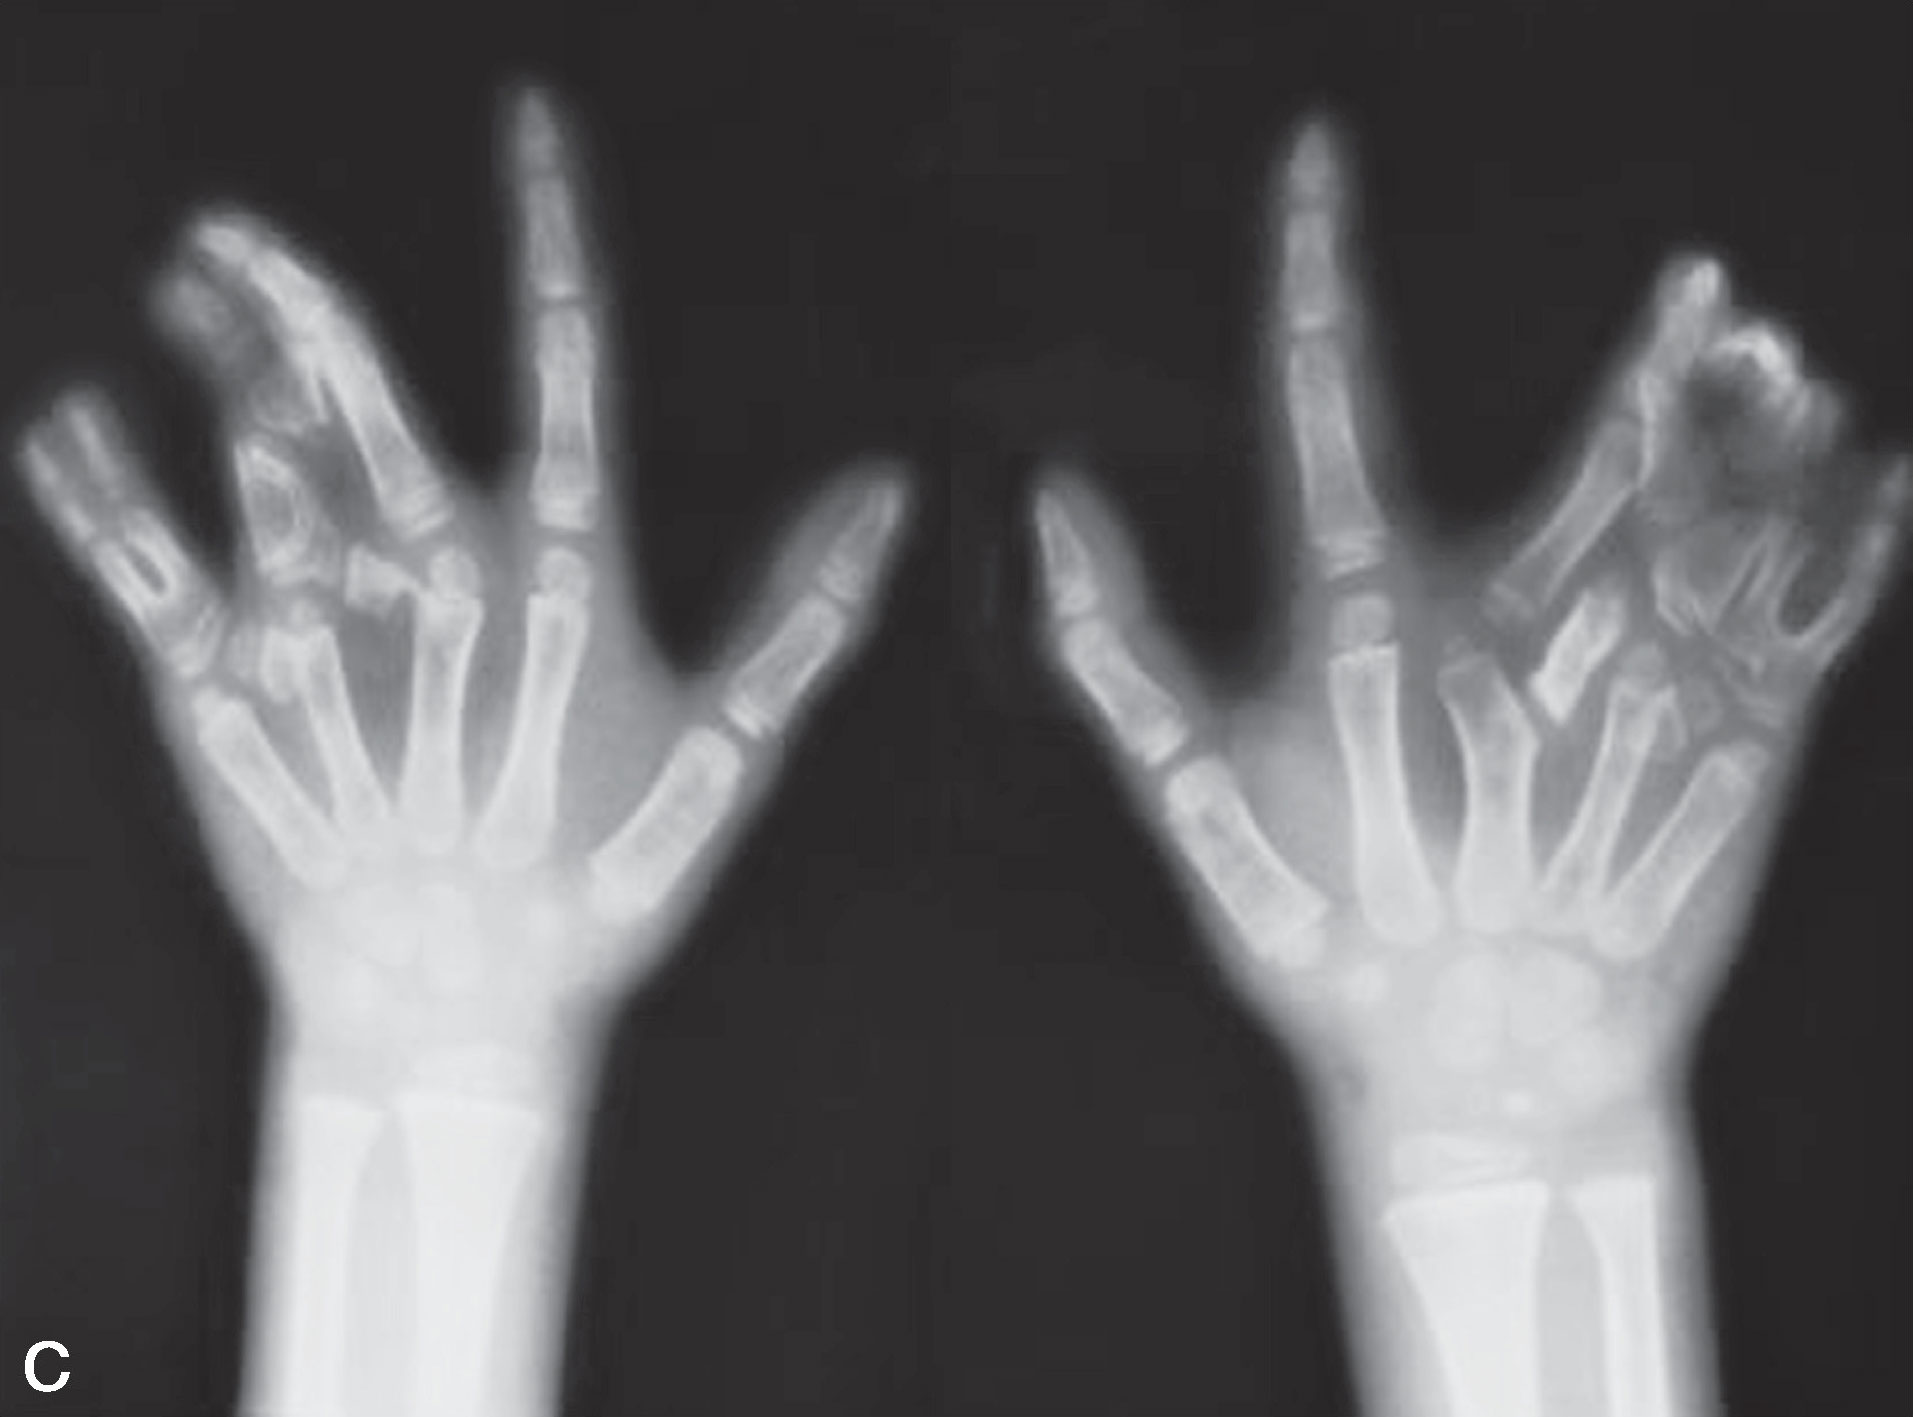

图2-3-14 骨关节严重畸形中央型多指病例6

A.双手中央型、尺侧多指并指;B.掌面观;C.X 线片显示骨关节结构广泛发育不良,根据实施治疗医生对畸形的认识和患儿家长的接受程度,可有多种手术设计,保留下来手指外形可有一定的改善,但功能较差